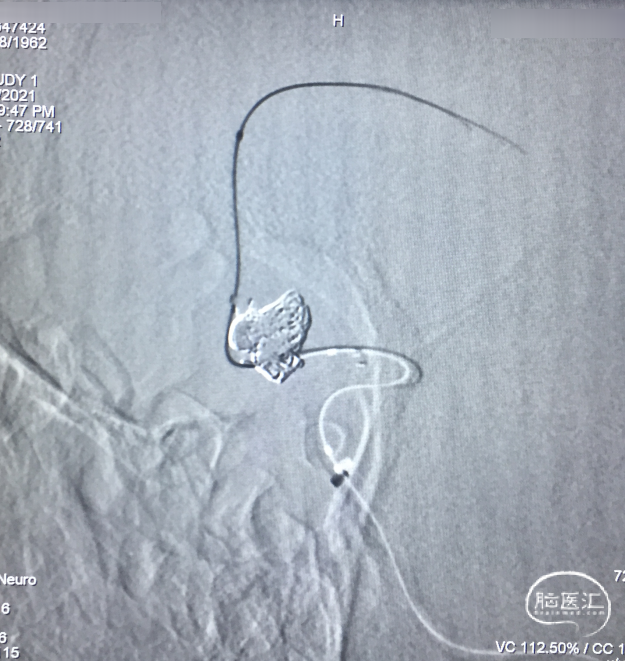

微导管到位

SL-10(直头)置于RACA A2,Atlas支架(直径3.0mm,较血管直径2.0mm大一号)到位,头端在RACA A2(左图);SL-10(头端S型)置于AcoAn左侧分叶(右图)。

支架释放

Atlas支架原位释放,头端打开良好,中部因较血管管腔大,可实现穹隆效果,以保护LACA A2流入道,尾端即将完全释放(左图);Atlas支架继续完全释放,尾端打开良好(右图)。

穿网孔超选

将直头SL-10穿过Atlas网眼超选入动脉瘤右侧分叶(左图),蒙片显示Altas形态及双微导管头位置,到达理想位置(右图)。